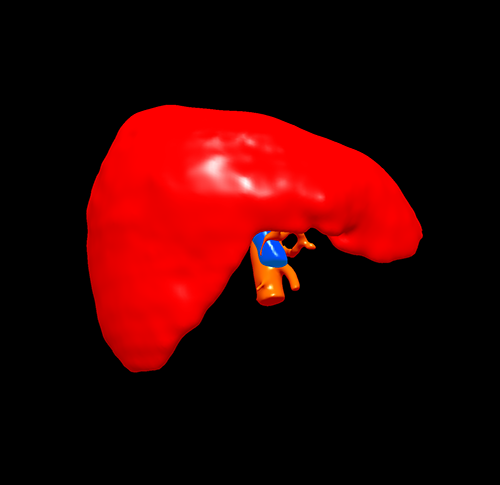

三维重建

S67肝癌--腹腔镜S67切除